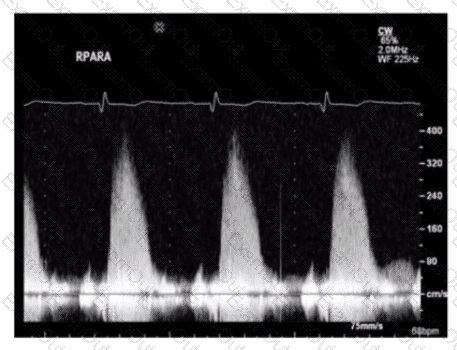

Which patient positioning is best for obtaining the waveform seen in this image obtained by a non-imaging transducer?